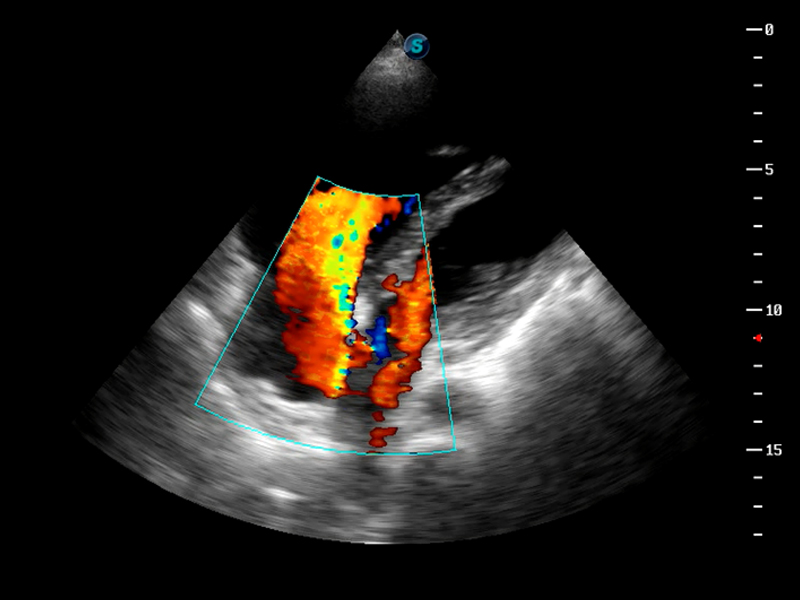

S9便携式彩色多普勒超声诊断仪是16877太阳集团研发的高端便携彩超设备,外观设计新颖、产品性能卓越。S9在便携超声领域采用了突破传统的触摸屏交互设计,并以先进的软件硬件技术和设计理念,为您带来清晰的图像质量、稳定的工作性能和便捷的操作体验。

AutoC智能血流追踪